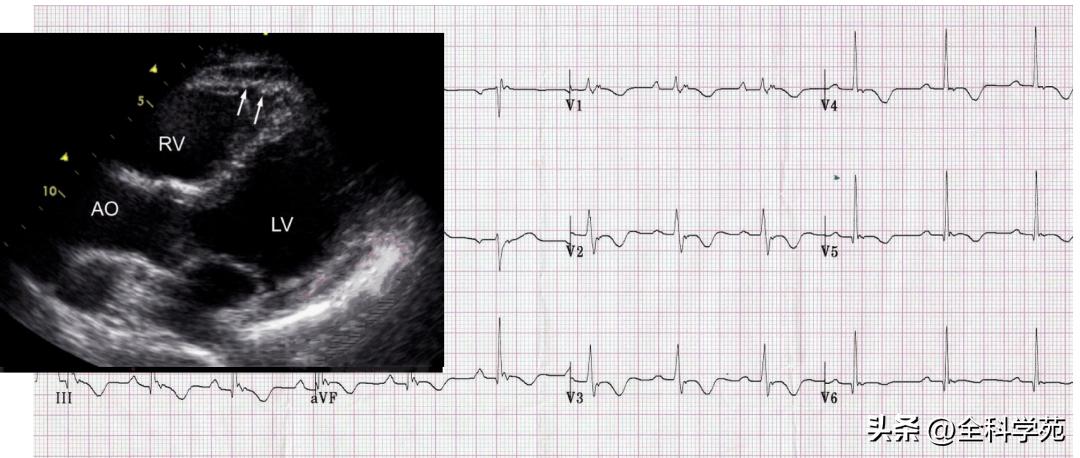

2. 致心律失常性右室心肌病

致心律失常性右室心肌病 (ARVC)是一种主要以右室心肌组织不同程度地被纤维组织所取代的心肌疾病,由于右心室心肌进行性被纤维脂肪组织所替代,右室部分心肌细胞萎缩、退化,在左心室及右心室心肌大部分除极后,病变区的心肌细胞仍有延迟的缓慢除极活动,造成室壁动作电位持续时间不一致,出现除极异常、复极障碍,患者以心律失常表现为主,包括室早、持续性和非持续性室速

- 如图可见Epsilon波,右胸导联T波倒置

- 心脏彩超提示左室长轴切面右室壁菲薄,心室波群右室扩大,右室壁活动明显降低,心肌活检显示病变心肌被脂肪细胞取代